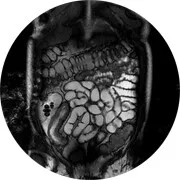

L’IRM est l’une des techniques d’imagerie médicale les plus récentes permettant d’étudier de nombreux organes sans utiliser les rayons X. Les images sont obtenues à l’aide d’un champ magnétique très puissant, d’ondes de radiofréquence et d’un système informatique complexe.

Les différentes techniques d’imagerie médicale dont on dispose ont chacune leurs avantages. Certains tissus, organes ou lésions ne sont visibles que par le biais de l’IRM. Cette dernière est l’examen de référence pour les pathologies neurologiques intracrâniennes (accident vasculaire, tumeurs, malformations, sclérose en plaques, maladies dégénératives du cerveau) ou de la moelle épinière. L’IRM permet également une très bonne analyse de l’ensemble des organes qui composent le système musculo-squelettique (colonne vertébrale, muscles, tendons, ligaments, articulations…). C’est aussi un examen de choix pour les maladies du cœur.